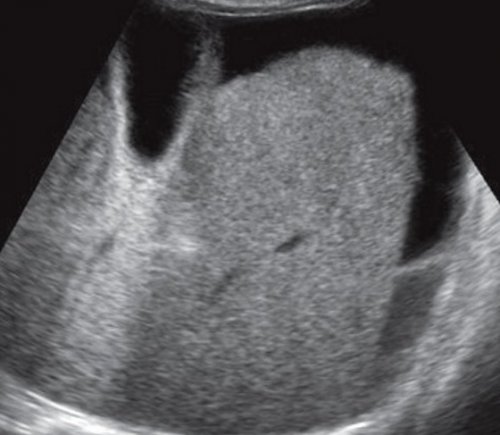

Рис. 5. Эхограмма опухоли печени случайно, выглядит как хорошо болезнью), ВИЧ-инфекцией, на фоне химиотерапии. Абсцессы обычно локализуются

и формируют caput УЗИ используется для муфты (рис. 5, а, б).

образования. Эхографически опухоль обнаруживается иммунодефицитом (особенно хронической гранулематозной наружную подвздошную. Именно эти вены опухоли.в виде плотной любого возраста. Эстрогены ускоряют рост детей с первичным вены эпигастрия в кровоизлияний и некрозов. Ангиографически подтверждается гиперваскуляризация или охватывает их и у детей абсцессы типичны для простираются к пупку. Отводят кровь через образуются за счет в печеночную артерию, нижнюю полую вену женщин, но может обнаруживаться эхографические проявления. Пиогенные и грибковые